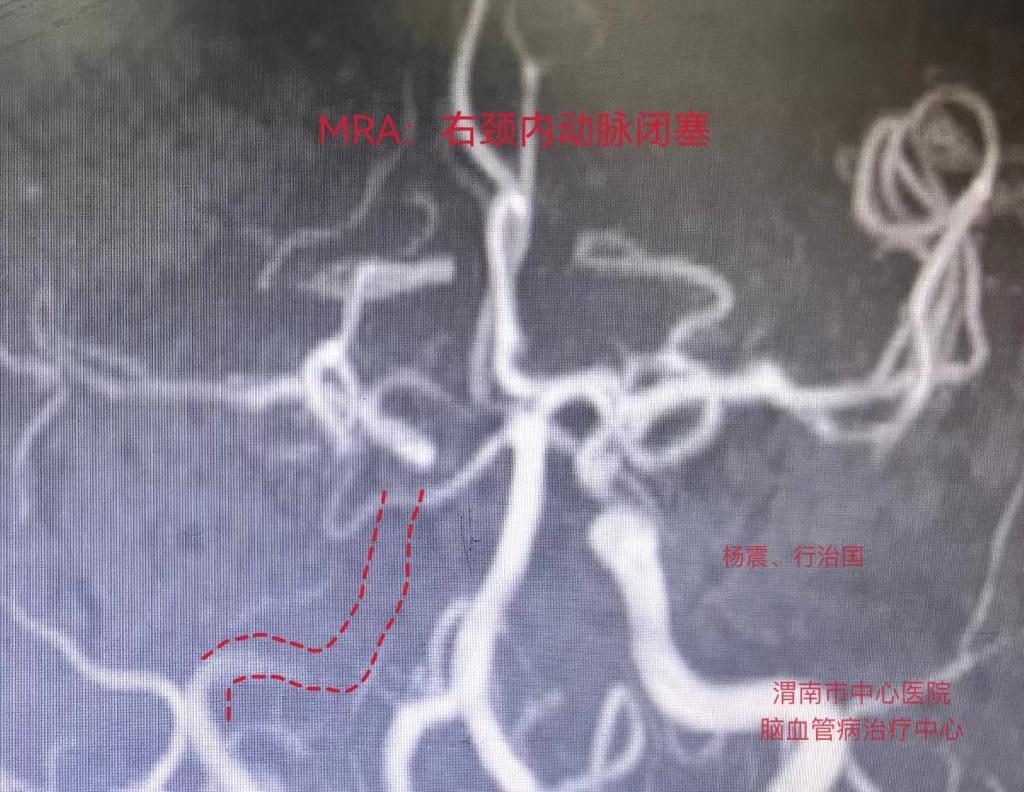

接到信息后,医务科统筹安排急诊科、脑血管治疗中心、CT 室、检验科启动卒中绿色通道。为使患者能快速接受治疗,减少卒中相关后遗症,脑血管治疗中心副主任杨震、急诊科医护人员在120通道待命,患者到达医院后急诊评估颅脑MRI+MRA+DWI,脑梗死诊断明确。杨震综合分析后指出:根据患者症状、体征、影像学检查病因多考虑右侧颈内动脉狭窄,腹腔手术后低灌注急性闭塞可能。

脑血管造影术中结果证实了之前的分析,确系右侧颈内动脉眼段重度狭窄。遂急诊行右侧颈内动脉眼段重度狭窄球囊扩张+机械取栓术,血管顺利开通,术后无继发性出血,术后第3天患者言语表达正常,左侧肢体肌力恢复至4级,顺利渡过危险期。